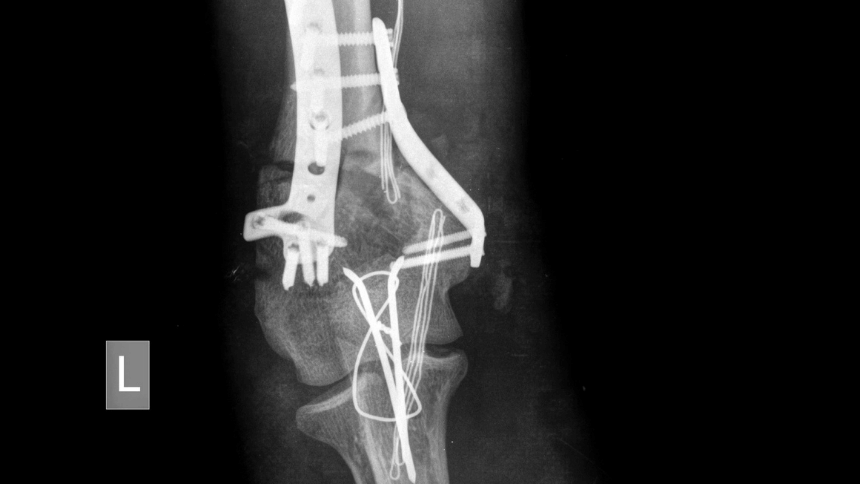

Možná chirurgická léčba seniorů

Chirurgické řešení je u seniorů nezbytné zejména tehdy, když je kost oslabená osteoporózou a běžné léčebné metody již nejsou dostačující.

Otevřená zlomenina neboli složená, je vážnější, protože kost při zlomení prorazí kůži. Před zafixováním do sádry se zlomenina často chirurgicky čistí, aby se odstranily nečistoty a snížilo riziko infekce.